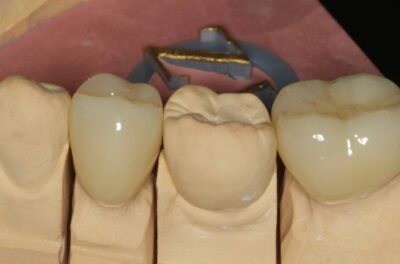

Протезирование коронками из диоксида циркония, после эндодонтического лечения — Исламов Л.А.(01.04.2026)